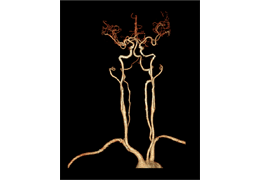

成像智能。

Eclipse 成像智能功能提供强大的处理能力和最佳质量的影像,同时减少质量错误并提高剂量效率。

凭借 AI、专有算法和先进的影像处理能力,提供出色的影像质量和无与伦比的诊断信心。

与标准影像处理相比,智能降噪功能可使客户降低辐射剂量,而不会损失影像质量。这在新生儿和儿科成像中尤其重要,在这种情况下以尽可能低的剂量成像至关重要。